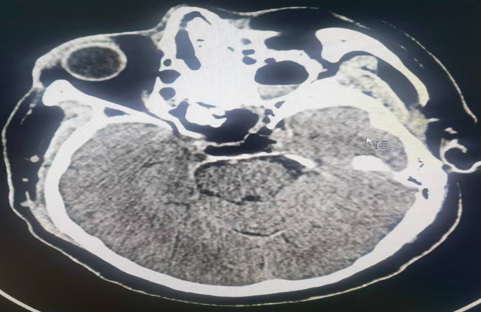

术后复查CT

肿瘤已彻底切除,无残留组织